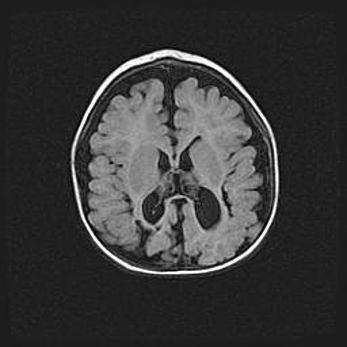

Наружная гидроцефалия с возможной атрофией височных областей.

Возраст: 28 дней

Вес: 3670 г

Пол: мужской

Окружность головы: 38 см

Срок гестации: 40 недель

Гидроцефалия головного мозга у новорожденных – это заболевание, которое характеризуется скоплением избыточного количества спинномозговой жидкости в желудочковой системе головного мозга в результате затруднения её перемещения от места выработки к месту поглощения в кровеносную систему или вследствие нарушения абсорбции. При открытой наружной форме гидроцефалии у новорожденных расширяются и переполняются субарахноидные пространства.

При нормотензивных  формах,  которые,  как  правило,  являются  следствием  перенесенных ишемических  повреждений  паренхимы  мозга,  возможно  сочетание микроцефалии  с нормотензивной гидроцефалией. В основе данных изменений лежит атрофия больших полушарий с преимущественной  локализацией  в  лобно-височных  областях.